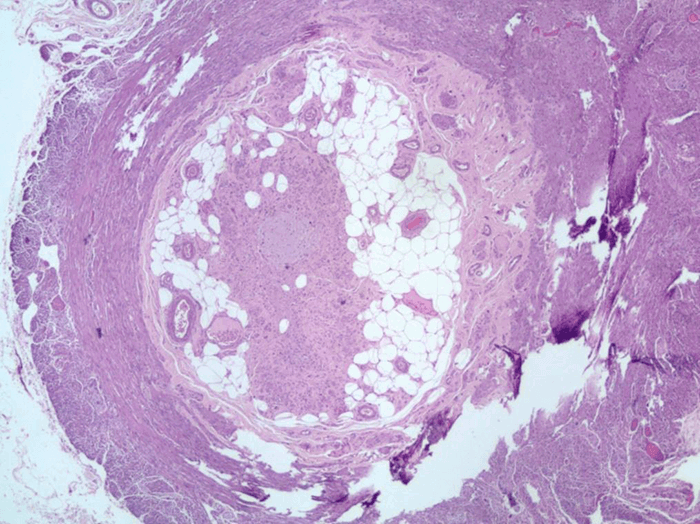

Fourteen lymph nodes were harvested, and all were negative for metastasis (Stage T4N0M0). The tumor was positive for neuron specific enolase (NSE) (Figure 2) and synaptophysin (Figure 3), but chromogranin A and CD56 negative. Histological examination of the appendix was normal (Figure 4).

Figure 4. Hematoxylin and eosin stain showing a normal appendix